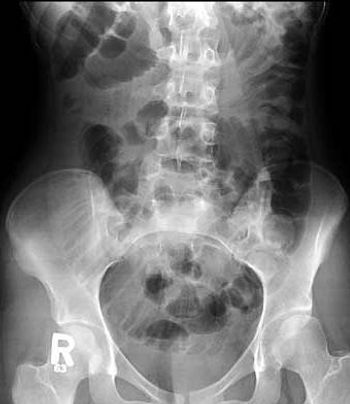

A 16-year-old female patient with repeated vomiting. First X-ray of the abdomen shows multiple dilated small bowel loops, represent distal small bowel obstruction. CT of the abdomen done for further evaluation.